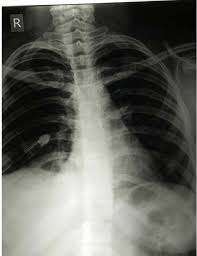

Pneumothorax / Case Report Covid 19 Associated Bilateral Spontaneous Pneumothorax A Literature Review In The American Journal Of Tropical Medicine And Hygiene Volume 103 Issue 3 2020 / Tension pneumothorax most commonly occurs in people with penetrating chest injuries.. This may be caused by physical trauma to the lung, such as a wound. Pneumothorax nursing interventions, treatment, pathophysiology nclex review for the different types of pneumothorax: There are several variations of pneumothorax. Pneumothorax is the medical term for a collapsed lung, a condition in which air or gas is trapped in the space surrounding the lungs causing the lungs to collapse. Also known as pneumothorax, collapsed lung is a rare condition that may cause chest pain and make it hard to breathe.

This is termed spontaneous pneumothorax. Pneumothoraces can be even further classified as simple, tension, or open. Pneumothorax nursing interventions, treatment, pathophysiology nclex review for the different types of pneumothorax: Pneumothorax, also called a collapsed lung, is when air gets between one of your lungs and the wall of your chest. It is reasonably common and has many different causes.

Scielo Brasil Pneumothorax As A Late Complication Of Covid 19 Pneumothorax As A Late Complication Of Covid 19 from minio.scielo.br In tension pneumothorax, patients are distressed with rapid laboured respirations, cyanosis, profuse diaphoresis, and tachycardia. The definition of a pneumothorax is an accumulation of air outside the lungs, but inside the chest wall. Tension pneumothorax most commonly occurs in people with penetrating chest injuries. In a healthy body, the lungs are touching the walls of the chest. Patients with a pneumothorax typically report dyspnoea and chest pain. A pneumothorax occurs when air leaks into the space between the lung and chest wall (called the pleural space). A small pneumothorax may cause few or no symptoms. Pneumothorax occurs when air enters the space around your lungs (the pleural space).

Other signals that the problem may be a collapsed lung are: Normally, the outer surface of the lung sits next to the inner surface of the chest wall. The lung and the chest wall are covered by thin membranes called pleura. It occurs when air accumulates between the parietal and visceral pleura inside the chest. Pneumothoraces can be even further classified as simple, tension, or open. A pneumothorax is an abnormal collection of air in the pleural space between the lung and the chest wall. Pneumothorax is defined as the presence of air or gas in the pleural cavity (ie, the potential space between the visceral and parietal pleura of the lung), which can impair oxygenation and/or. A pneumothorax occurs when air leaks into the space between your lung and chest wall. The pressure causes the lung to give way, at least partly. Pneumothorax is classified as spontaneous or traumatic. Hemothorax occurs when there is blood in that. This air pushes on the lung, which makes it collapse. The air accumulation can apply pressure on the lung and make it collapse.

While secondary pneumothorax is caused by an underlying pulmonary disease, the spontaneous type occurs in healthy individuals without obvious cause. When there is no apparent cause, the condition is known as spontaneous pneumothorax. Other signals that the problem may be a collapsed lung are: Pneumothorax is classified as spontaneous or traumatic. Normally, the outer surface of the lung sits next to the inner surface of the chest wall. There are several variations of pneumothorax. It occurs when air accumulates between the parietal and visceral pleura inside the chest. A tension pneumothorax can cause complete collapse of the nearby lung and can push the heart and major blood vessels to the other side of the chest. A collapsed lung requires immediate medical care. Patients with a pneumothorax typically report dyspnoea and chest pain. This air pushes on the outside of your lung and makes it collapse. The lung and the chest wall are covered by thin membranes called pleura. Also known as pneumothorax, collapsed lung is a rare condition that may cause chest pain and make it hard to breathe.

Pneumothorax And Pneumomediastinum In Covid 19 A Case Series The American Journal Of The Medical Sciences from els-jbs-prod-cdn.jbs.elsevierhealth.com A collapsed lung requires immediate medical care. Other signals that the problem may be a collapsed lung are: Patients with a pneumothorax typically report dyspnoea and chest pain. In a healthy body, the lungs are touching the walls of the chest. Pneumothorax is classified as spontaneous or traumatic. A pneumothorax is commonly known as a collapsed lung. A pneumothorax is an abnormal collection of air in the pleural space between the lung and the chest wall. This air pushes on the outside of your lung and makes it collapse.

Patients with a pneumothorax typically report dyspnoea and chest pain. Pneumothoraces can be even further classified as simple, tension, or open. Pneumothorax is defined as the presence of air or gas in the pleural cavity (ie, the potential space between the visceral and parietal pleura of the lung), which can impair oxygenation and/or. In a healthy body, the lungs are touching the walls of the chest. The definition of a pneumothorax is an accumulation of air outside the lungs, but inside the chest wall. It is reasonably common and has many different causes. A pneumothorax is a collection of air outside the lung but within the pleural cavity. A pneumothorax can be a complete lung collapse or a collapse of only a portion of the lung. A pneumothorax occurs when air leaks into the space between the lung and chest wall (called the pleural space). This air pushes on the lung, which makes it collapse. Also known as pneumothorax, collapsed lung is a rare condition that may cause chest pain and make it hard to breathe. A large pneumothorax can squash the lung and cause it to collapse. This is termed spontaneous pneumothorax.